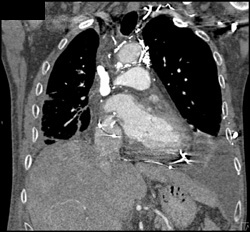

SVC Occlusion With Collaterals